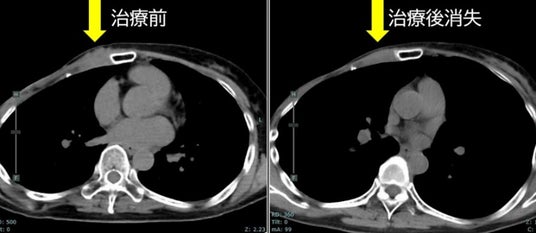

・FDG-PET陽性の浅在性腫瘍に対するBNCT(jRCTs031240204)治療4例目:再発乳がん

治療前約37mmの腫瘍が、治療3カ月後の画像診断で消失しています。

また、もともと基準値内(25以下)だった腫瘍マーカー(CA15-3)は20.9から10.7まで低下しています。